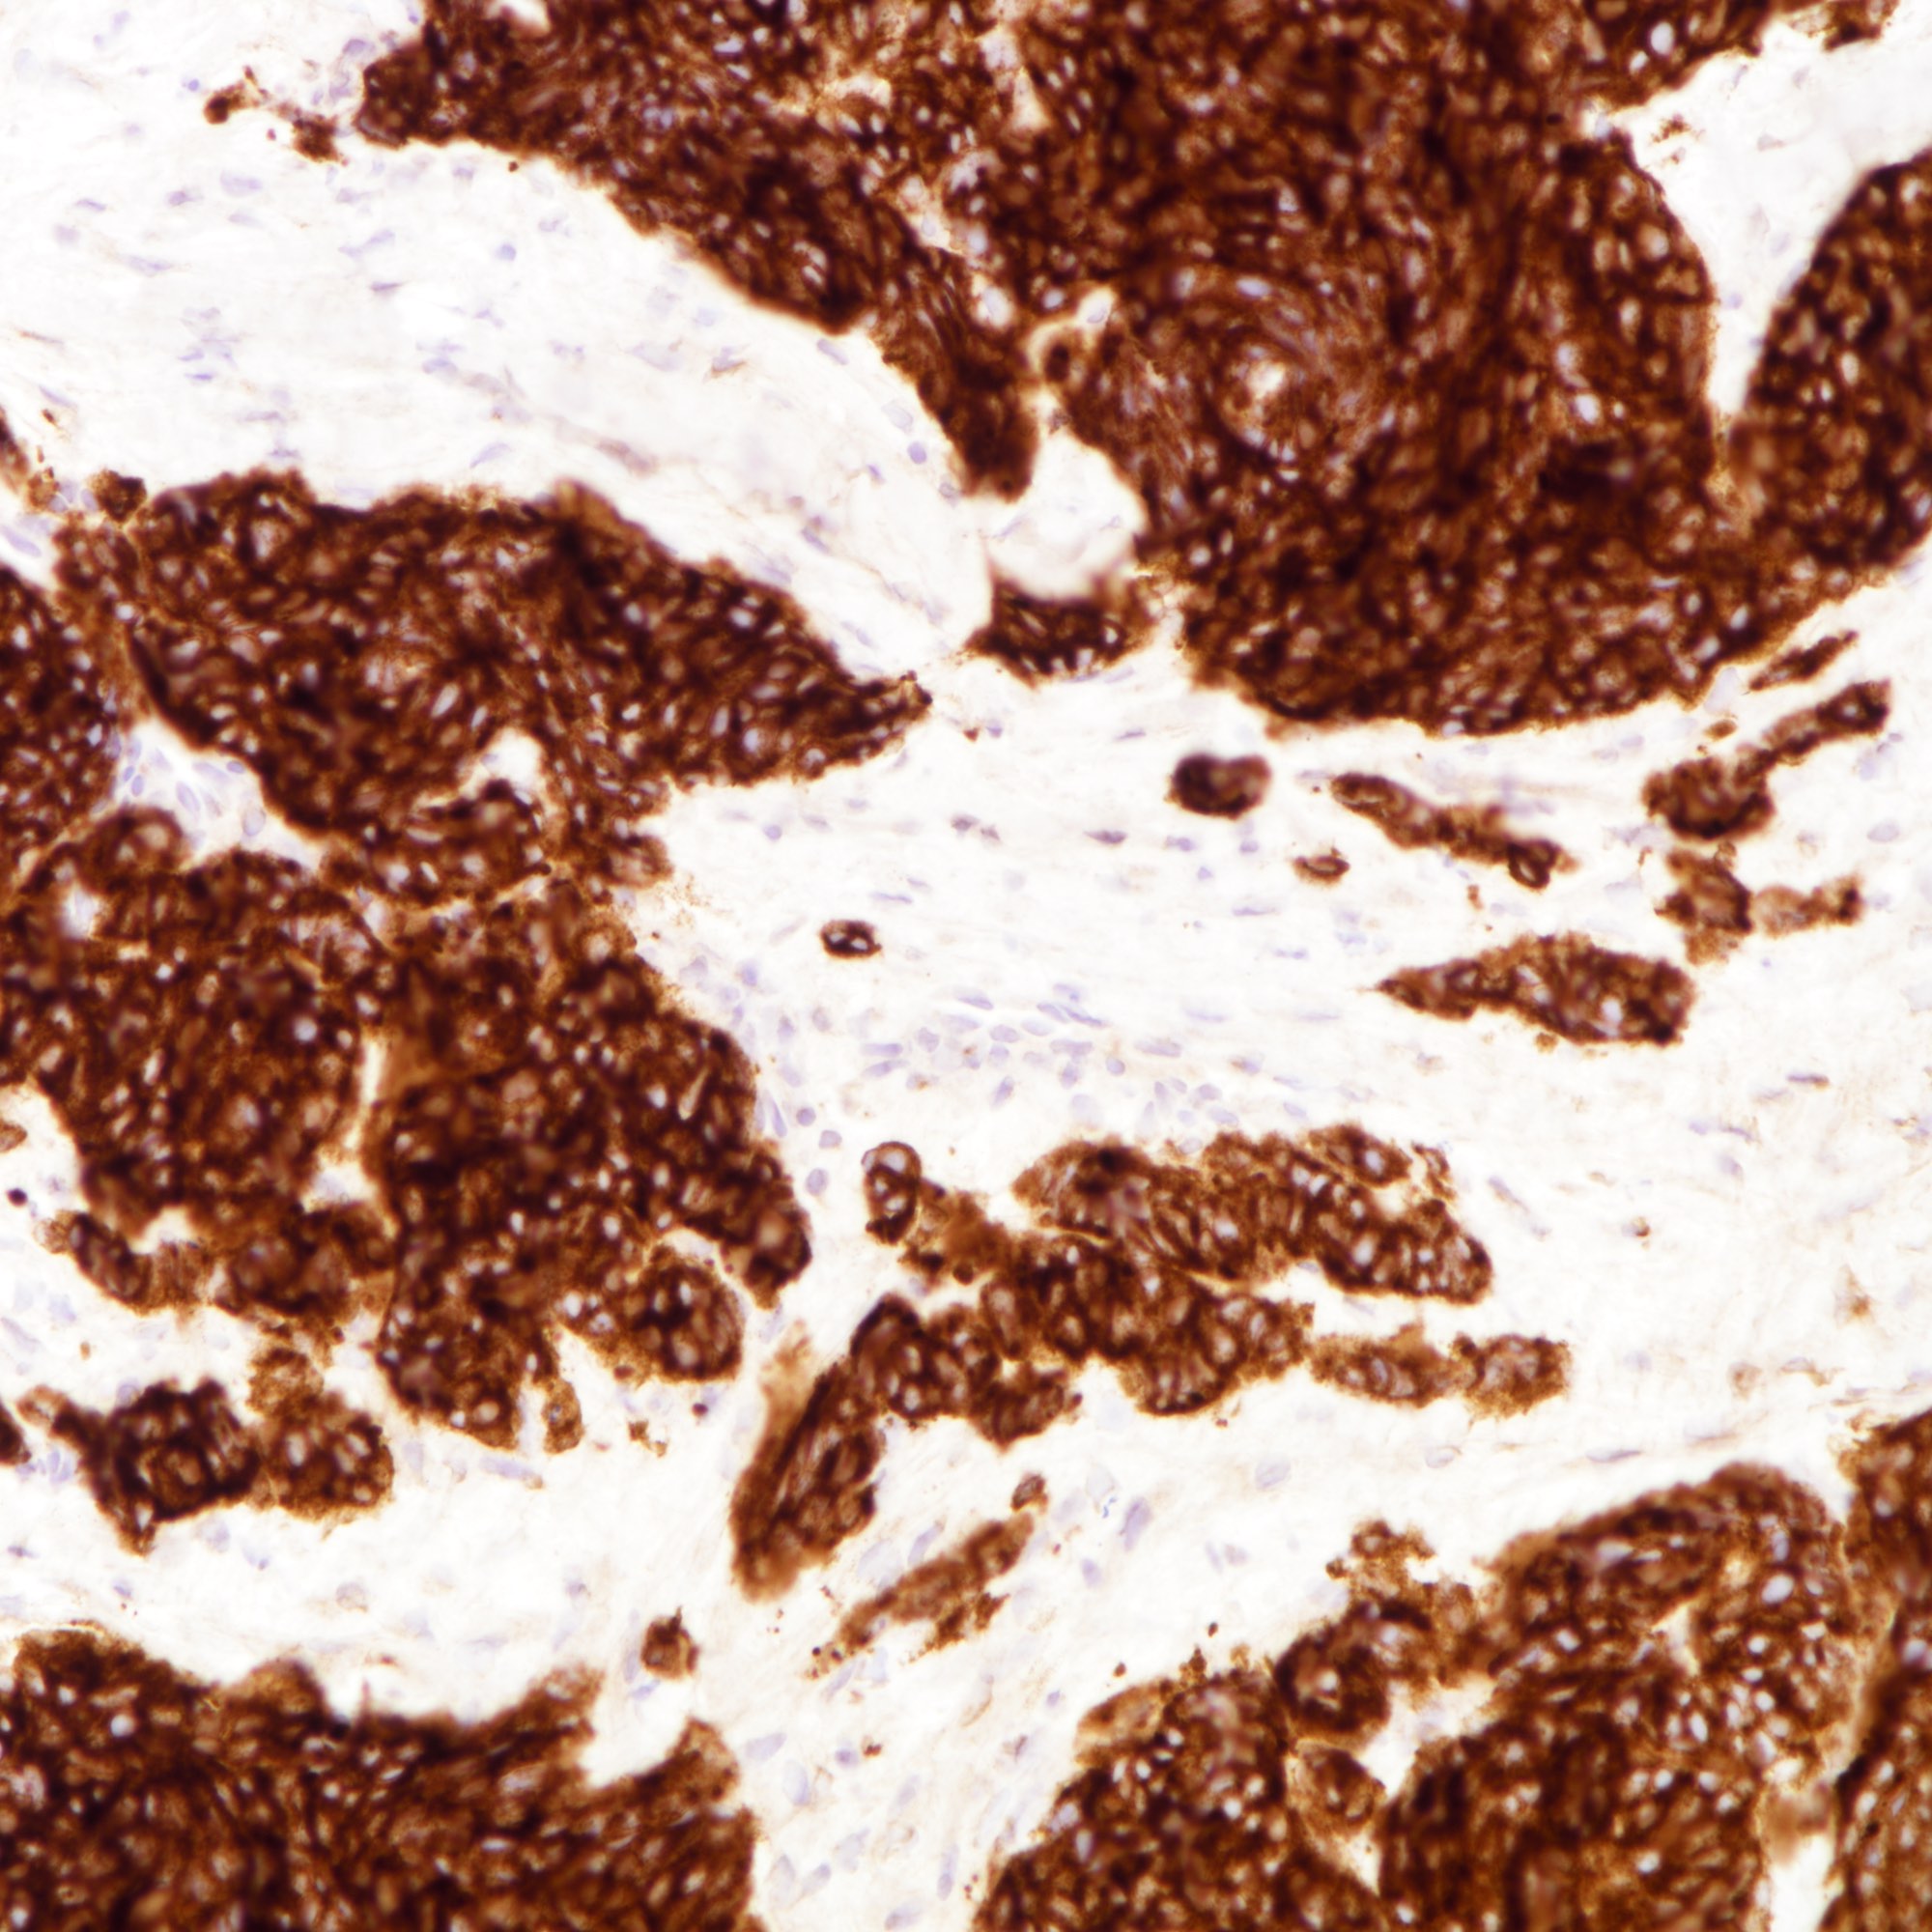

Contributed by Joshua J.X. Li, M.B.Ch.B., Gary M. Tse, M.B.B.S. and Kristen E. Muller D.O.

Small cell carcinoma

Large cell carcinoma

Positive stains

- Cytokeratins:

- Neuroendocrine markers:

- The tumor cells are diffusely positive for synaptophysin and focally positive for chromogranin.

- The tumor cells are diffusely positive for synaptophysin and focally positive for chromogranin.